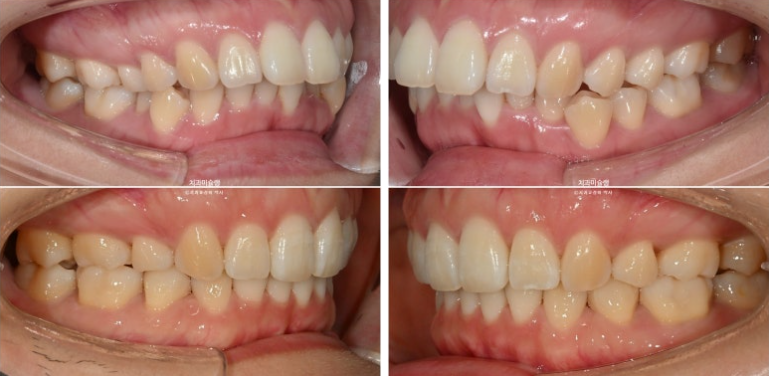

돌출입 교정을 위해 멀리 지방에서 오신 환자분입니다.

윗니 돌출이 심합니다.

아랫니 기준으로 약 1센치가 더 튀어나와 있습니다.

위 아래 앞니 간격은 1-2mm 가 정상입니다.

아래 치열은 덧니가 심한 상황입니다.

골격분석 결과 심한 상악골 전방 돌출을 동반한 골격성 2급 부정교합 입니다.

상악골 과잉에 의한 돌출은 돌출입 교정 중에서도 난이도가 높습니다.

상악과 하악의 골격 부조화가 심해 아래턱이 상대적으로 뒤로 밀려있는 상태여서 위 앞니 각도를 이상적으로 유지하기가 쉽지 않습니다.

입이 안 다물어질 정도의 윗니 돌출과 심한 아래 덧니를 해결하려면 작은어금니 4개 발치는 불가피합니다.